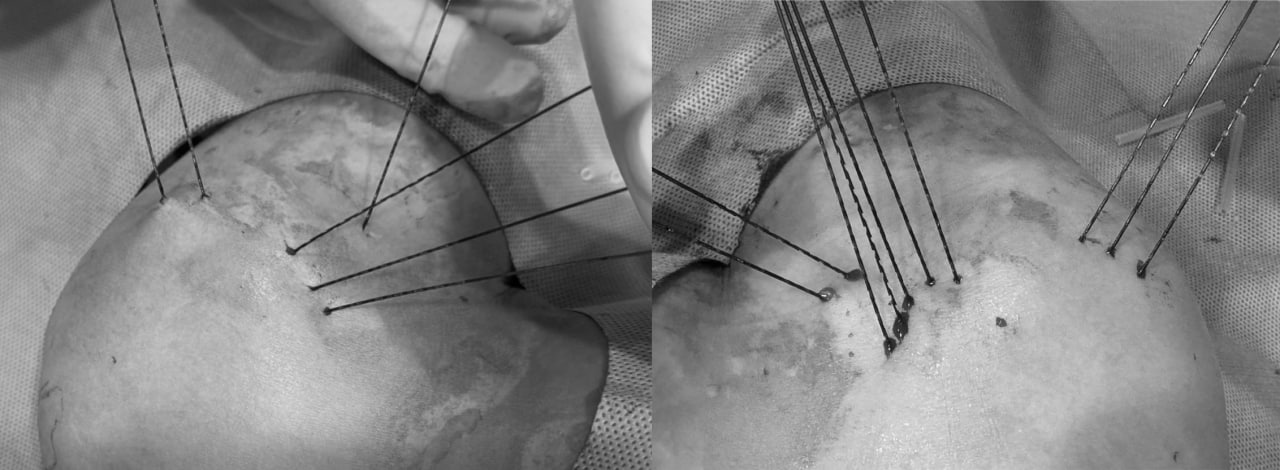

축소봉합술 시술사진

인대의 손상 정도와 양상에 따라 최소 4개, 최대 8개 까지 봉합사가 삽입됩니다.

파열된 부위의 인대를 촘촘하게 모아 재생을 촉진시킵니다.